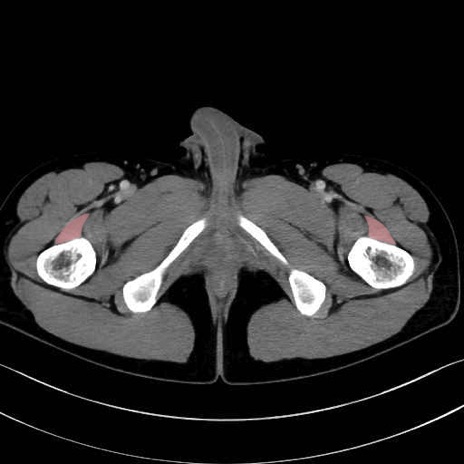

中間広筋 (Vastus intermedius)